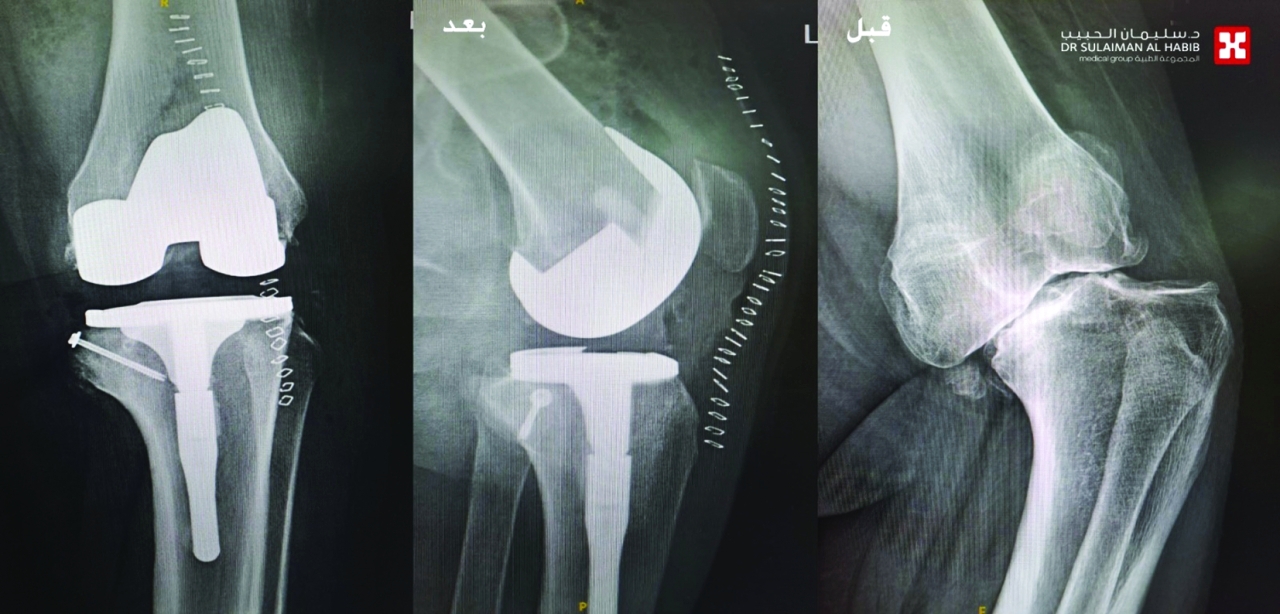

ولكن دون جدوى، ودائماً ما كانت حالته تُرفض من قبل الأطباء، نتيجة التعقيد بعظام الركبتين لديه، مفيداً بأنه تم إخضاع المريض لحزمة من الفحوصات الطبية بالأشعة الرقمية «Digital X-rays»، والتصوير المقطعي «C.T Scan»، وكشفت النتائج عن وجود خشونة شديدة من الدرجة الرابعة بكلتا الركبتين، وإصابته بتشوه خلقي نادر يعرف باسم «Blount Disease»، وهو المتسبب في الأعراض التي عانى منها منذ الصغر.

وأشار الدكتور لؤي الخطيب إلى أنه بعد تجهيز المريض، أجريت له عمليتان جراحيتان، تم فيهما استبدال مفصلي الركبة، وتعديل وإصلاح التقوسات لكلتا الساقين، وقد تكللت جهود الفريق الطبي بالنجاح، بدون أية مضاعفات، نقل بعدها إلى جناح التنويم، وبدأ في برنامج علاج طبيعي تأهيلي مكثف، موضحاً أن المريض تلقى رعاية طبية فائقة على مدار الـ 5 أيام، واستعاد استقامة الساقين، وأصبح يمشي بصورة طبيعية، وقد خرج من المستشفى معافى.